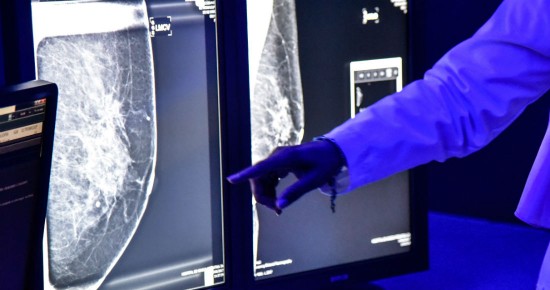

| Ya es oficial: la Cofepris advierte que los implantes mamarios de Allergan pueden causar cáncer. | ||||||

| En conjunto con dicha empresa, la dependencia determinó llevar a cabo el retiro voluntario del mercado de los implantes mamarios texturizados y expansores de tejido BIOCELL, en los cuales se incluyen las marcas NATRELLE y MICROCELL, en todos los modelos y lotes, debido al posible riesgo de linfoma anaplásico de células grandes (LACG). | ||||||

En conjunto con dicha empresa, la dependencia determinó llevar a cabo el retiro voluntario del mercado de los implantes mamarios texturizados y expansores de tejido BIOCELL, en los cuales se incluyen las marcas NATRELLE y MICROCELL, en todos los modelos y lotes, debido al posible riesgo de linfoma anaplásico de células grandes (LACG). Esta Comisión Federal está dando seguimiento puntual al retiro del mercado nacional para ejecutar las medidas de seguridad que correspondan en estricto apego a la legislación sanitaria vigente, para reducir riesgos en la salud de la población, aseguró en un comunicado. De acuerdo con las autoridades, los insumos cuentan con los siguientes registros sanitarios en México: https://www.sinembargo.mx/wp-content/uploads/2019/07/captura-de-pantalla-2019-07-31-a-las-13-35-36.png Con esta medida, la Cofepris se suma a las acciones de control sanitario que diversas autoridades de salud internacionales están llevando a cabo en relación al retiro de mercado de implantes mamarios de la empresa Allergan. Asimismo, hizo una serie de recomendaciones para las pacientes que hayan recibido algún implante mamario, entre las que se encuentra que en caso de presentar cualquier síntoma o signo (por ejemplo: aumento brusco del volumen de la mama, dolor, inflamación, nódulo/masa, secreciones, ulceración) se debe acudir con el cirujano plástico tratante, para su revisión y diagnóstico. También pidió consultar al cirujano plástico sobre los riesgos del tipo de implante que recibieron y en su caso, la frecuencia con que deben acudir a chequeo para la realización de los estudios de imagen que procedan, y seguir las indicaciones del especialista. Mientras que a los los cirujanos plásticos, estéticos y reconstructivos solicitó dar seguimiento puntual a las personas en las que se llevó a cabo una cirugía de implante mamario, notificar a la Cofepris mediante el sistema en línea de notificación de incidentes adversos de dispositivos médicos, todos los casos asociados a linfoma anaplásico de células grandes (LACG) relacionados con el uso de los implantes mamarios, en la siguiente liga electrónica: https://www.gob.mx/cofepris/acciones-y-programas/sistema-en-linea-de-notificacion-de-incidentes-adversos-de-dispositivos-medicos . A su vez, llamó a no utilizar los implantes antes citados y en caso de contar con algunos de ellos en existencia, contactar a la empresa Allergan para llevar a cabo el retiro del producto, en los siguientes puntos de contacto: teléfono: 01 800 2530791, correo electrónico: medinfo.mexico@allergan.com . La Cofepris establece como medida de protección, no adquirir ni usar los productos citados en el comunicado, ya que pueden generar un riesgo a la salud, finalizó. RETIRAN IMPLANTES MAMARIOS EN EL MUNDO El pasado 24 de julio, el fabricante de implantes mamarios Allergan Inc. anunció el retiro en todo el mundo de sus modelos texturizados debido a un vínculo con un tipo raro de cáncer. La Administración de Alimentos y Medicamentos de Estados Unidos (FDA, por sus siglas en inglés) dijo que exigió el retiro después de recibir información según la cual los implantes Biocell de Allergan con superficie texturizada están relacionados con un número desproporcionado de casos de linfoma. Francia, Australia y Canadá ya tomaron medidas similares. La FDA no recomienda a las mujeres con implantes que se los hagan retirar si no sufren trastornos. Los implantes Biocell incluyen una superficie texturizada para impedir el movimiento y minimizar el tejido cicatrizado. Esos modelos abarcan el 5 por ciento del mercado estadounidense. La amplia mayoría de los implantes mamarios usados en Estados Unidos son de superficie lisa. Las autoridades de salud vincularon los implantes texturizados con el cáncer por primera vez en 2011. No es un cáncer de mama sino un linfoma que crece en el tejido cicatrizado alrededor de las mamas. Crece lentamente y en general se lo trata con éxito mediante el retiro quirúrgico de los implantes. En mayo, la FDA dijo que el peligro no era tal que merecía una prohibición nacional de los implantes. Pero el miércoles dijo que nuevos datos muestran un vínculo directo del cáncer con los implantes de Allergan, aunque no con otros implantes texturizados. Una vez que las pruebas indicaron que el producto de determinado fabricante parecía estar vinculado directamente con trastornos significativos e incluso la muerte del paciente, la FDA tomó medidas, dijo la subjefa del organismo, Amy Abernethy, en un comunicado. Según la FDA, las cifras más recientes muestran que más del 80% de los 570 casos confirmados de linfoma están vinculados con los implantes de Allergan. Estas cifras incluyen los 116 casos detectados en los últimos meses. ¿HASTA QUÉ PUNTO ES DAÑINO? Según el informe de la Administración de Alimentos y Medicamentos de EU, de los 573 casos de pacientes afectados en todo el mundo por este tipo de cáncer, el así llamado linfoma anaplásico de células grandes, 481 se atribuyen a los implantes de Allergan. De otros 33 casos letales, 12 fueron causados por estos implantes. Cabe señalar que no es el contenido de los implantes lo que provoca la formación de las neoplasias malignas, sino su cubierta texturizada. Además de las texturizadas existen también cubiertas lisas, pero éstas no permiten que el dispositivo se mantenga en su lugar con la misma eficacia que las texturizadas. Según el citado organismo estadounidense, los síntomas principales del linfoma anaplásico de células grandes incluyen dolor e hinchazón en el pecho. En su comunicado Allergan recomendó a los pacientes que en caso de que tengan alguna duda, consulten con sus cirujanos sobre los posibles riesgos de su tipo de implantes. Los implantes mamarios texturados rellenos de solución salina y silicona y los expansores de tejido Biocell ya no se distribuirán ni venderán en ningún mercado en el que estén disponibles actualmente. Con efecto inmediato, los profesionales sanitarios no deben seguir implantando implantes mamarios texturados Biocell ni expansores de tejido, y los productos no utilizados deben devolverse a Allergan, anuncia la empresa. -Con información de AP y RT |